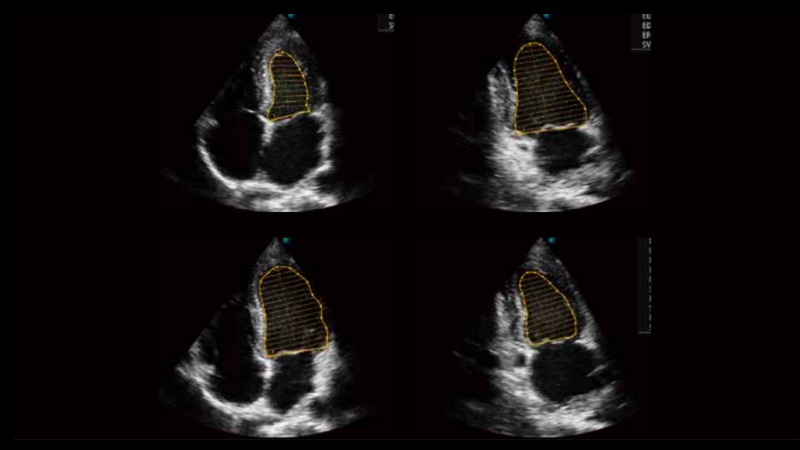

自動(dòng)識(shí)別前后壁內(nèi)膜厚度,為心血管疾病早期評(píng)估提供快速準(zhǔn)確依據(jù)。

自動(dòng)識(shí)別收縮和舒張末期心肌內(nèi)膜,自動(dòng)計(jì)算射血分?jǐn)?shù)EF值。